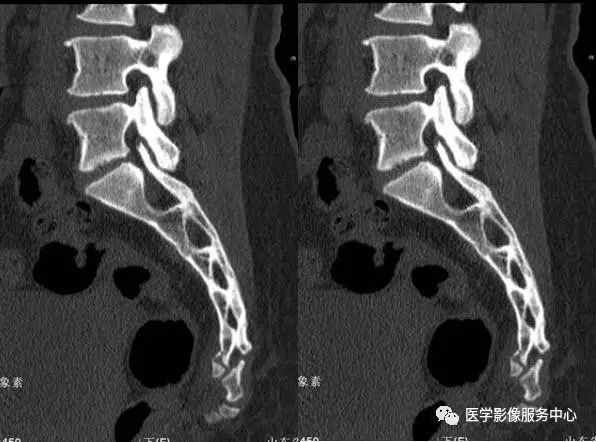

附病例(X线+CT):

病人女性,外伤后骶尾部疼痛,dr片示骶尾关节对应关系差,骶5椎体欠规则。ct重建示骶5椎体粉碎性骨折!

CT: